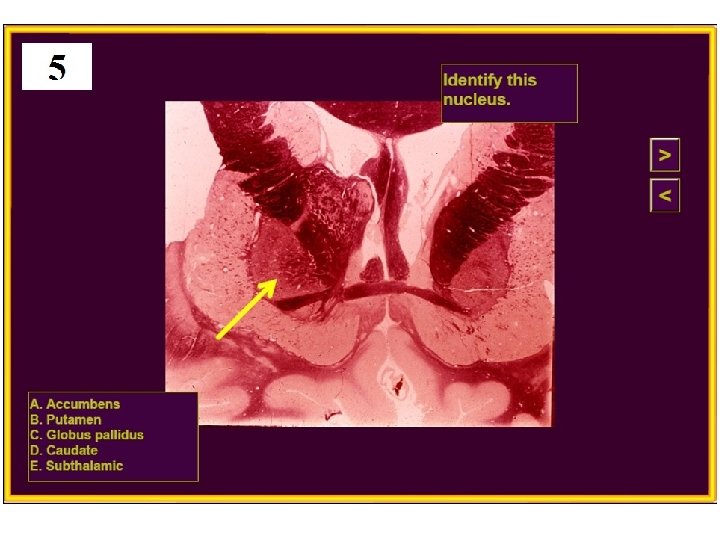

20. Huntington’s disease is caused by degeneration of which nucleus? A) Subthalamic B) Globus pallidus C) Substantia nigra D) Caudate E) VPL